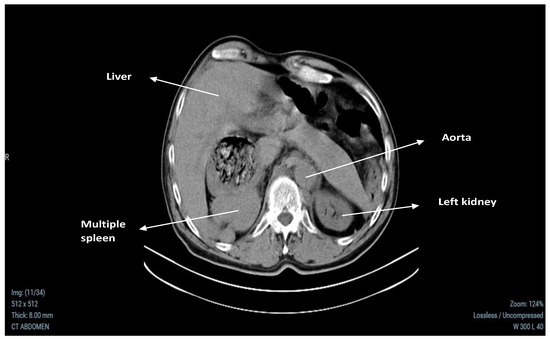

2.3. Abdominal CT Results

| Other Imaging Findings | CT scan revealed liver cysts and multiple splenic nodules; normal kidney size with cysts. |